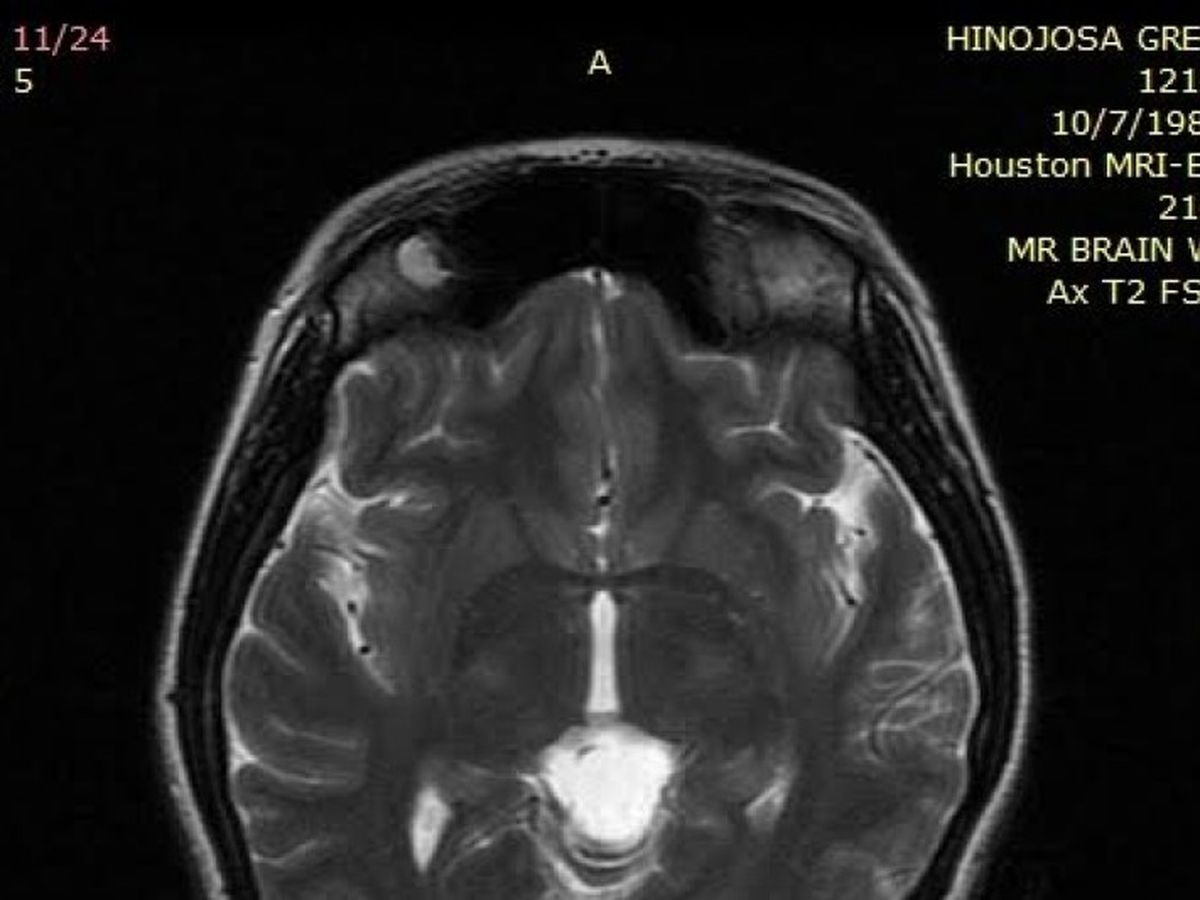

In 2013 I delivered my second child and started experiencing extremely painful headaches that would induce vomiting and dizziness. My OBGYN immediately sent me to a neurologist. When explaining my symptoms he swore that I was experiencing an epidural leak (a leak of the fluid around the brain and spinal cord). Through an MRI I was diagnosed with a 2.1 cm pineal cyst. I was so incapacitated that I was unable to care for my newborn, 5yr old daughter, husband or myself. For three years I've lived on pain pills, on December after experiencing new symptoms such as cold sweats, unable to keep balance standing up or walking and even my vision turning completely black, I knew something wasn't just right on 01/22/16 after another MRI as usual I received a call from neurologist saying everything was still the same, and that he was going to change my medication AGAIN.I knew that was just not right, after searching I came across a neurosurgeon here in Houston who is known for his outstanding medical history, on March 1, 2016 I call to ask for an appointment and was asked to send my medical records and the they were scheduling appointments for the end of May, on March 8th after sending my medical records I receive a call from Dr. Kim’s office asking me to watch a webinar on his website about Arachnoid Cyst and that Dr Kim wanted to see me as soon as possible March 15th since it took me by surprise I asked if it could be the following week and they schedule me for March 22, 2016. At my appointment I found out, that what I thought for three years was a pineal cyst was actually and arachnoid tumor that was in the pineal gland which are rare, he explained to me that for sure my symptoms were due to my cyst growing and that I needed to get surgery done before my symptoms start worsen, they will have to put a drain inside my head that will stay there for the rest of my life due to 40% this type of cysts/tumors tend to come back, he has done over 300 surgeries on pineal cyst removals and only five on arachnoid tumors. Due to my symptoms getting worse and the cyst growing I need to get surgery soon, unfortunately this type of surgery is very expensive and due to the timing I have to get it done is almost impossible for us to raise that amount money without your help. We want to Thank You in advance for your donations, for your help, support and for your all your prayers.